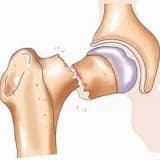

Braxial iflic, körpənin onurğa beyninin boyun səviyyəsindən başlayan sinir strukturlarının uzanması nəticəsində həmin tərəfdə, qolda və əldə müxtəlif şiddət dərəcələrində inkişaf edən əzələ zəifliyi və ya iflicidir.

Ehtimal 1000 yeni doğulmuş uşaqda 1-4 arasında dəyişir. Onun baş vermə ehtimalını artıran faktorlar arasında çoxdöllü hamiləlik, körpənin böyük ölçüdə olması, uzun və çətin doğuş, körpənin ayaqları ilə doğum kanalına girməsi, yəni çəpər olması saymaq olar.

Bu vəziyyət əksər körpələrdə 2 yaşa qədər kortəbii olaraq gerilə bilər. Bu ehtimal körpənin müayinəsi ilə proqnozlaşdırılır. Bununla belə, bütün hallarda, körpə birgə hərəkətləri qorumaq və daha aktiv şəkildə istifadə edə biləcəyi yuxarı ətrafa sahib olmaq üçün müalicə almalıdır. Öz-özünə geriləyə bilməyən və ya geriləməyəcəyi proqnozlaşdırılan körpə və uşaqlarda bəzi əməliyyatlar qolun daha aktiv istifadəsinə imkan verir.